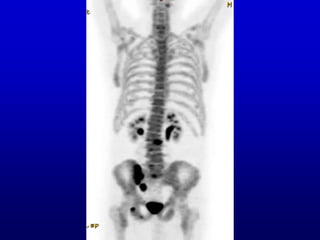

What is your impression as to the

side of the sacroiliac lesion?

1. Right SI?

2. Left SI?

3. Can’t tell.

What is yourimpression as to the side of the sacroiliac lesion? 1. Right SI? 2. Left SI? 3. Can’t tell.

• #28 Time for more audience participation. Which side is the sacroiliac lesion on. Ready? (Show it twice.) Do you have an impression?

• #29 It’s the same case, but with a difference. Something called depth weighting has been applied, and I’ll explain that. As a result, now you can tell anterior from posterior, and are more likely to see the display as rotating counterclockwise, which corresponds with the true story of the patient, whose lesion is on the right, not the left.

• #30 To illustrate re anterior and posterior. Remember, I said that the original ambiguity occurred because the anterior and posterior images were the same, except for one being the mirror image of the other. This is a MIP, in which that situation has been changed. The anterior and posterior look different. Now you see the spine well in the posterior and the breastbone well in the anterior. Show that. Remember, in the first bone scan that I showed, the one in 2D, anterior and posterior looked different because of distance and the shadow of the tissues in between. In the modified MIP that I am showing you here, the computer has put in the shadows artificially, by the process called depth weighting. If you now see the sacroiliac lesion as being on the right, it is what is true for the patient, because you are now better able to perceive the movie as going counterclockwise rather than clockwise